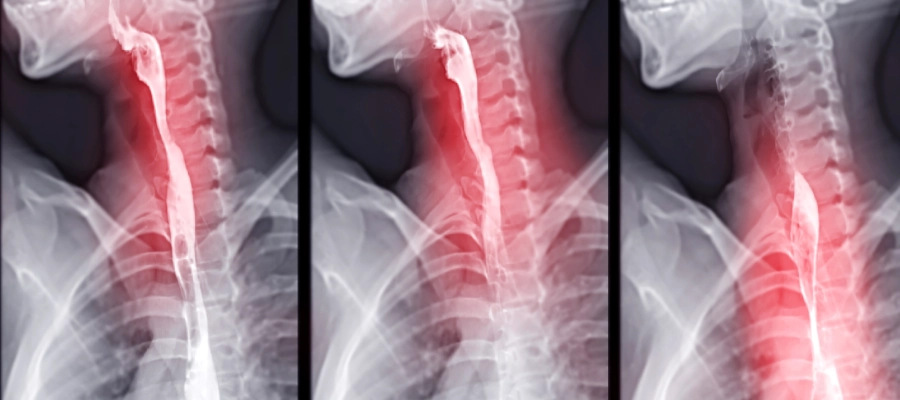

Özofagus ve Mide Röntgeni (Baryum Yutma Testi)

Bu test özofagustaki anatomik değişiklikleri görüntülemek için kullanılır. Röntgen ışınları altında tespit edilebilen sıvı bir ilacın yutulması ve yemek borusundan geçişi esnasında görüntüsü elde edilir.